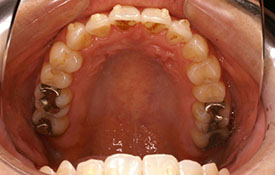

インビザラインの治療例:CASE-2

| プロフィール | 15歳 男性 |

|---|---|

| 所見 | アメリカから転院されて来られた方です。 インビザラインで上下顎の矯正治療を開始し下顎はアメリカで終了しており、上顎のみ治療の後期を担当しました。 アイライナーの装着は、1日平均22時間ほどでした。 |